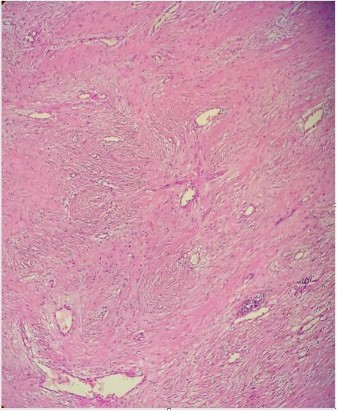

Microscopic analysis revealed myofibroblastic proliferation with infiltrative borders near to spleen capsule, without parenchymal involvement (Figure 1b, 1c). On higher magnification there were uniform, elongated, spindle cells with fascicle arrangement and thin-walled blood vessels with perivascular edema (Figure 1d). No nuclear atypia or mitoses were found. Immunohistochemistry revealed nuclear positivity for β-catenin stain favoring the diagnosis of desmoid type fibromatosis (Figure 1e). Some of the cells showed SMA positivity, while CD34, S100 and CD117 were negative. Proliferative marker Ki67 was low.

Figure 1b: Microscopic view of DF with spleen parenchyma (HEx40).

Figure 1c: Infiltrative margin in fat tissue (HEx40).